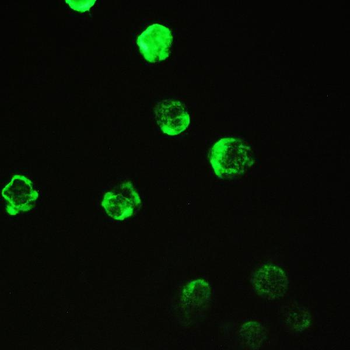

10 μg, 100 μgCYPA Rabbit Polyclonal Antibody [orb100498]

FC, IF, IHC-Fr, IHC-P, WB

Bovine, Canine, Porcine, Rabbit

Human, Mouse, Rat

Rabbit

Polyclonal

Unconjugated

50 μl, 100 μl, 200 μlFKBP52 Antibody: APC [orb147210]